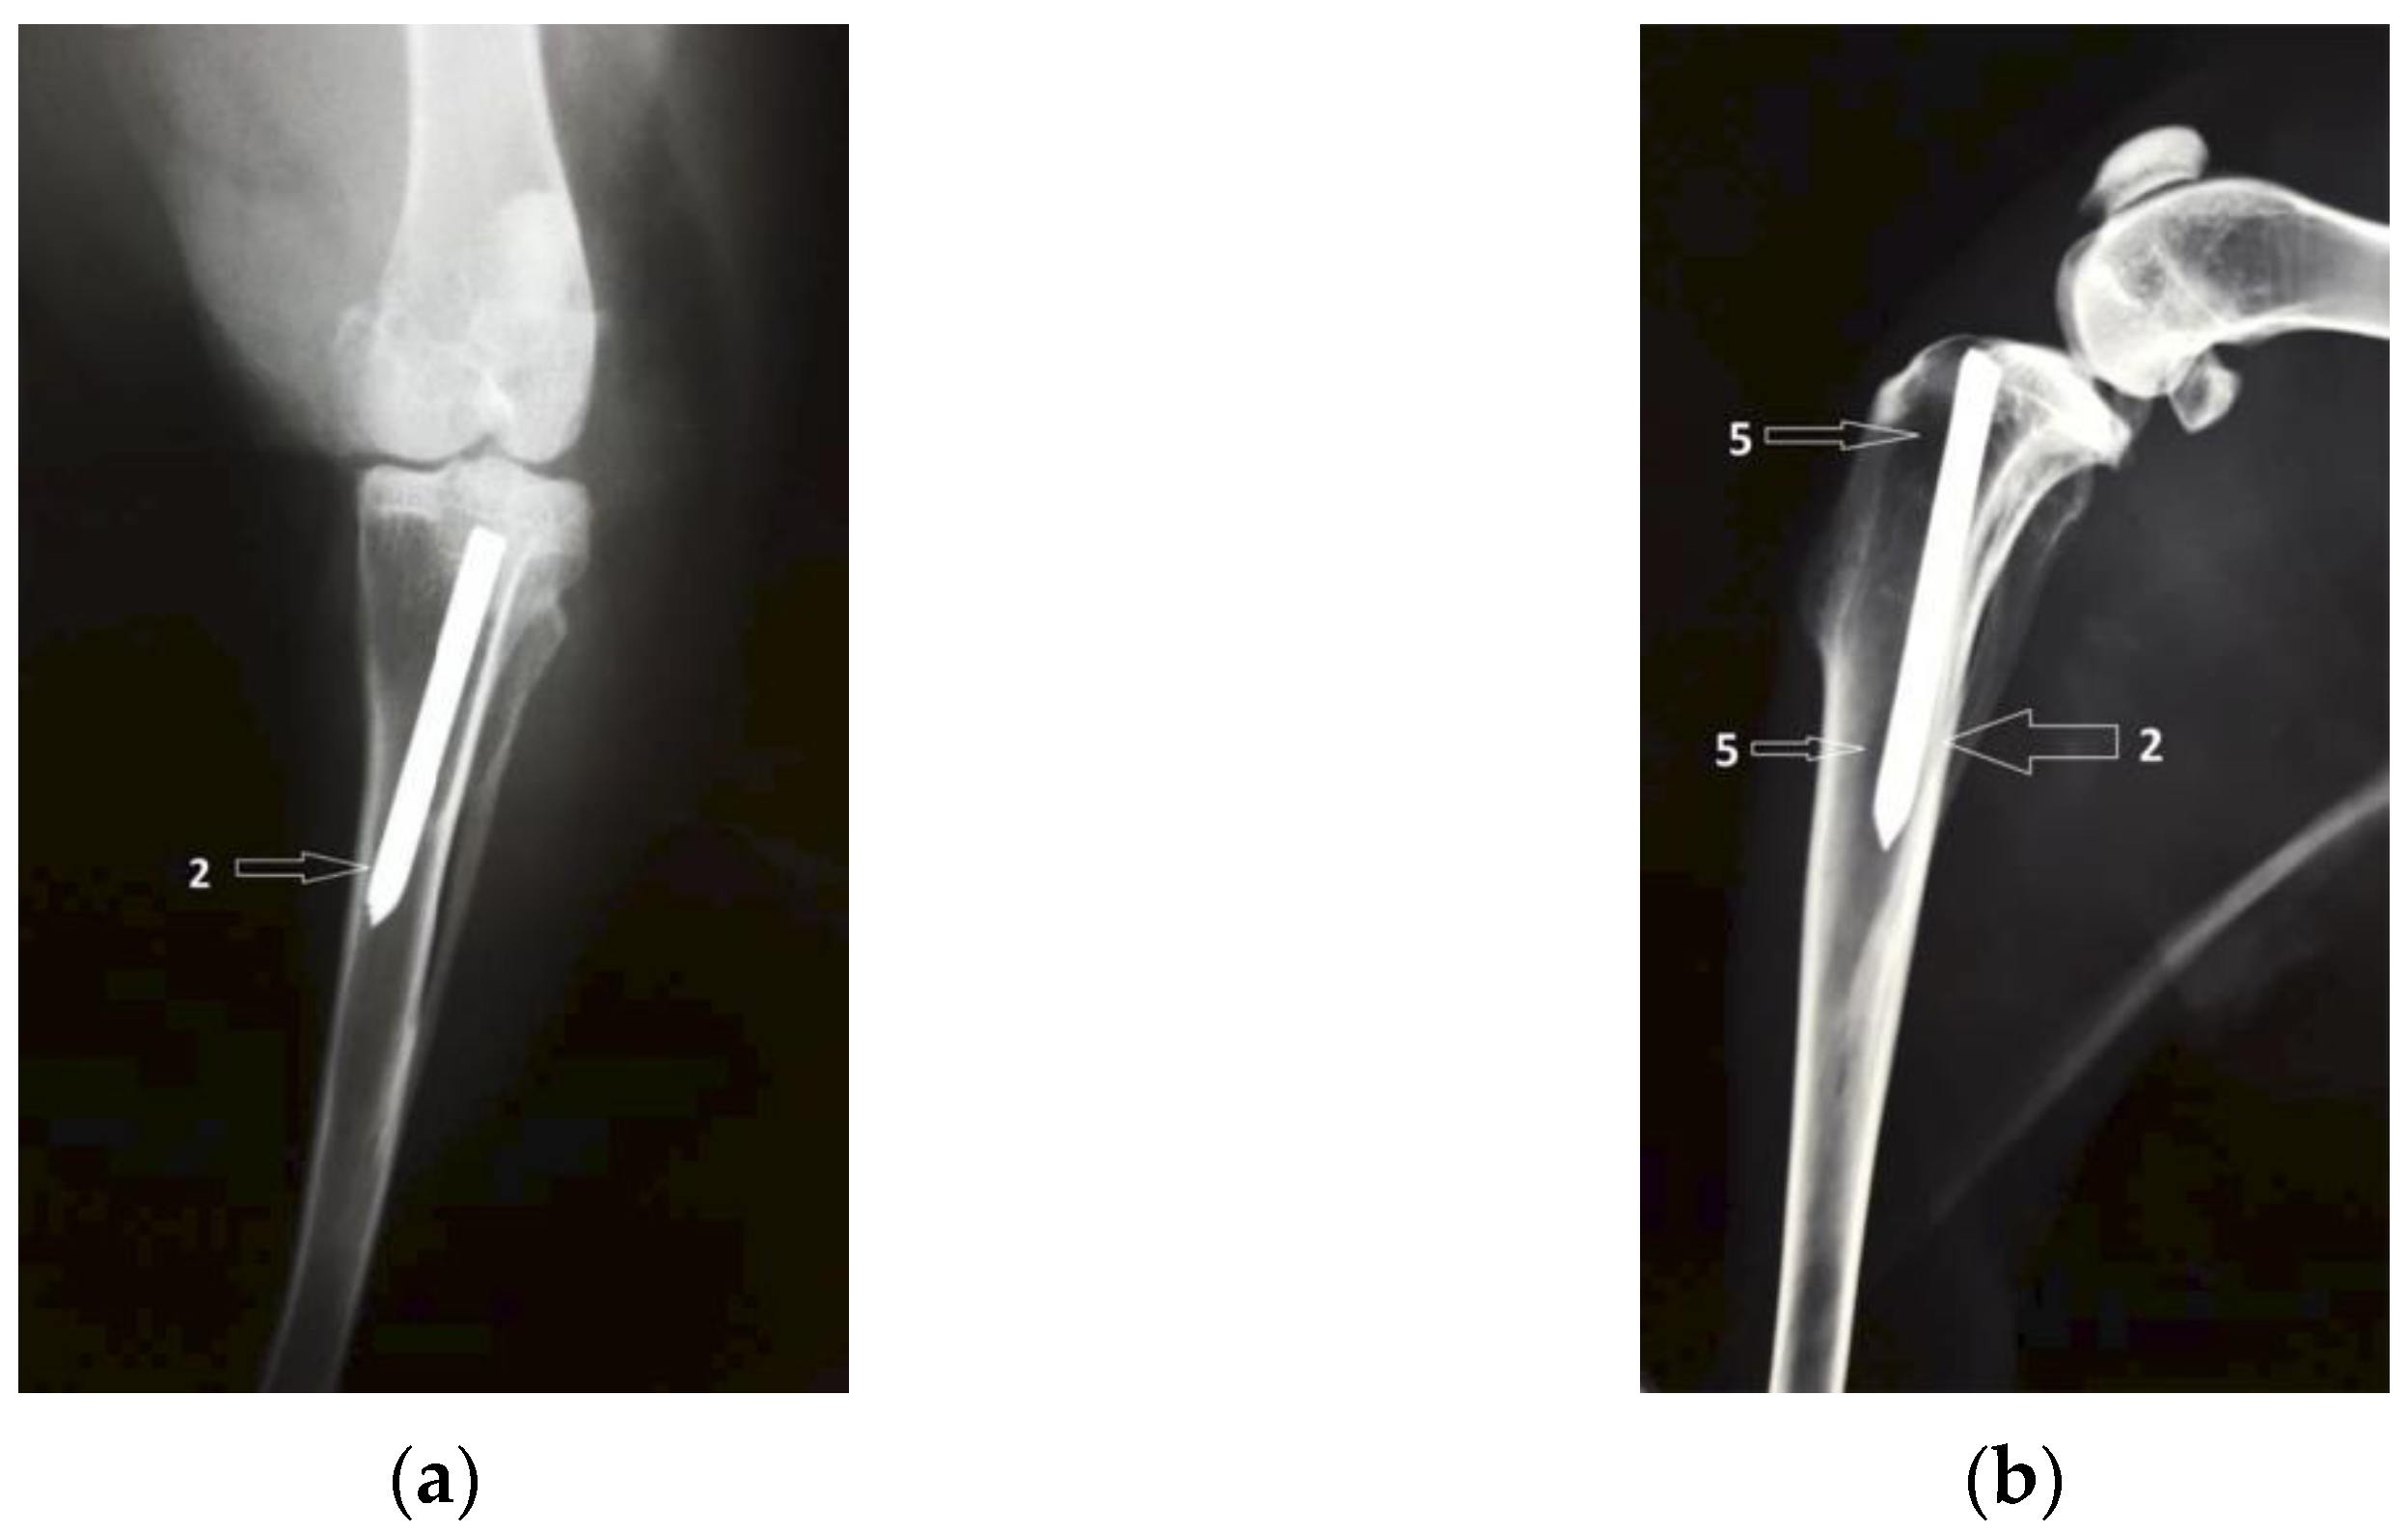

3.1. Radiological Followup